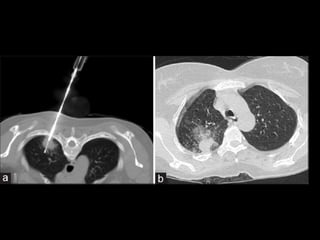

CT Angiogram Sign